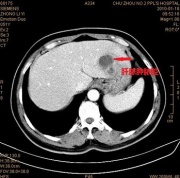

| 2014年1月17日 (五) 15:12 | CT.jpg (文件) |  |

41 KB | Admin | 1 | |